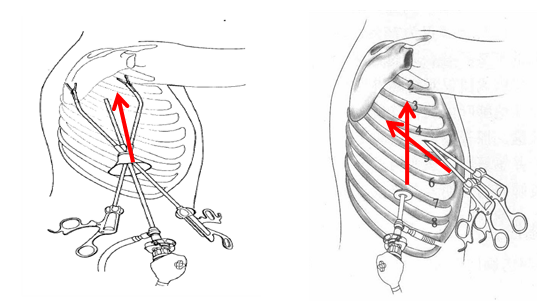

“神队友”奥利给!苏大附一院胸外科团队与机器人携手完成肿瘤切除...

“神队友”奥利给!苏大附一院胸外科团队与机器人携手完成肿瘤切除...